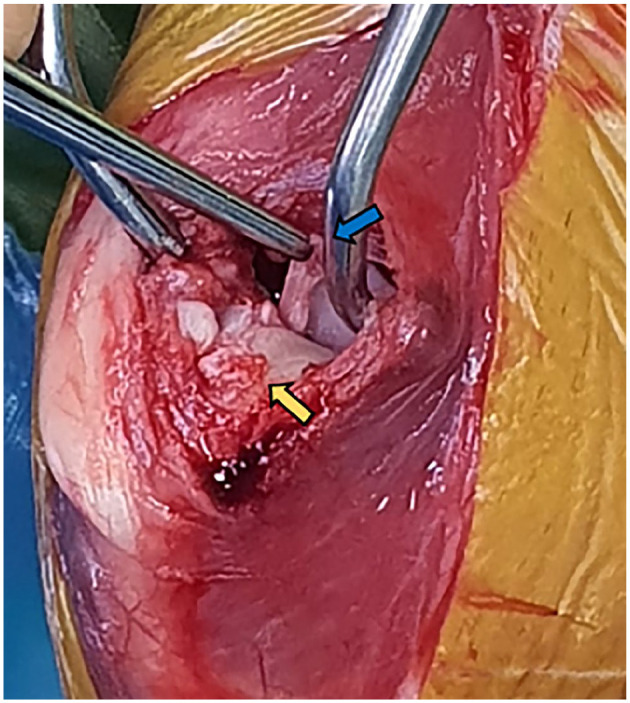

病例摘要:一只 11 岁的雌性阉割短毛猫因外伤性右跗关节松弛而转诊接受手术治疗。在全身麻醉的情况下,对患病跗关节进行了骨科检查,发现关节积液、颅尾和旋转不稳定。X光检查发现胫骨相对于股骨的头颅移位和髌下垫征。术中观察到两条十字韧带完全断裂,内侧和外侧半月板的中端和尾端明显断裂。两条副韧带看起来完好无损。切除了受伤的十字韧带残余部分,并进行了内侧和外侧尾骨半月板切除术。胫骨平台平整截骨术(TPLO)解决了胫骨头尾不稳的问题。术中对跗关节的评估显示,胫骨头侧平移、内旋和外旋以及尾侧牵引试验阳性的不稳定性持续存在。为解决持续存在的胫骨颅内翻和内旋问题,采用了外侧增强缝合术。为了成功中和因尾交叉韧带缺损而导致的颅内和外旋不稳定性,在三枚干扰螺钉的辅助下进行了内侧增强缝合。跗关节稳定得以实现。术后使用改良罗伯特-琼斯绷带包扎24小时。手术效果极佳,成功恢复了肢体功能:本病例报告首次记录了猫科动物外伤性跗关节松弛修复术,该手术结合了矫正性胫骨截骨术和关节外增高术。值得注意的是,该病例介绍了通过内侧和外侧增强缝合实施TPLO的新技术,以解决多向跗关节不稳定的问题。

Case summary: An 11-year-old female neutered domestic shorthair cat was referred for surgical management of a traumatic right stifle luxation. Orthopaedic examination of the affected stifle under general anaesthesia revealed joint effusion and craniocaudal and rotational instability. Cranial displacement of the tibia with respect to the femur and infrapatellar pad sign were identified on radiography. Intraoperatively, complete rupture of both cruciate ligaments and marked disruption of the mid and caudal poles of the medial and lateral menisci were observed. Both collateral ligaments appeared intact. The remnants of the injured cruciate ligaments were removed, and medial and lateral caudal hemimeniscectomies were performed. A tibial plateau levelling osteotomy (TPLO) was performed to address the craniocaudal stifle instability. Intraoperative assessment of the stifle revealed persistent instability with cranial tibial translation, internal and external rotation, and a positive caudal draw test. A lateral augmentation suture was employed to address the persistent cranial tibial translation and internal rotation. To successfully neutralise caudocranial and external rotational instability secondary to the caudal cruciate ligament deficiency, a medial augmentation suture was placed with the aid of three interference screws. Stifle stability was achieved. A modified Robert-Jones bandage was kept on for 24 h postoperatively. An excellent outcome was achieved, with successful limb function restoration.